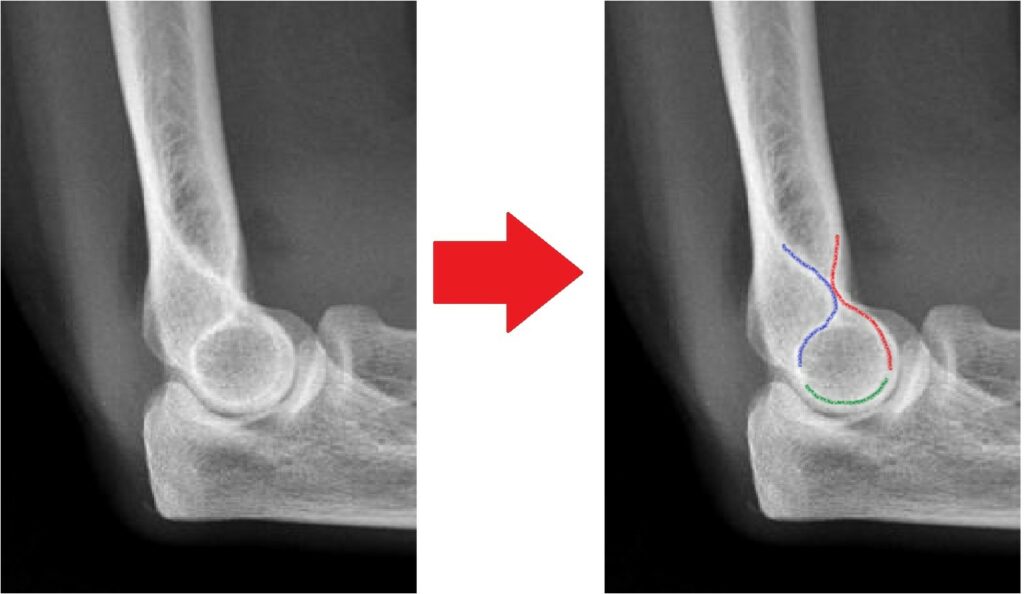

[toggle title=”Anterior Humeral Hat” state=”close”]

Lateral grafide humerus ön yüzeyine paralel ve bitişik çekilen çizgi kapitulumun 1/3 ortasından geçmelidir.

Bu hattın öne ya da arkaya yer değiştirmesi suprakondiler humerus kırığını destekler.

Aynı zamanda suprakondiler kırık hattıyla beraber posterior yağ yastıkçığı bulgusu da görülmekte

Bununla beraber kırık hattı ve posterior yağ yastıkçığı bulgusu da seçilmekte.